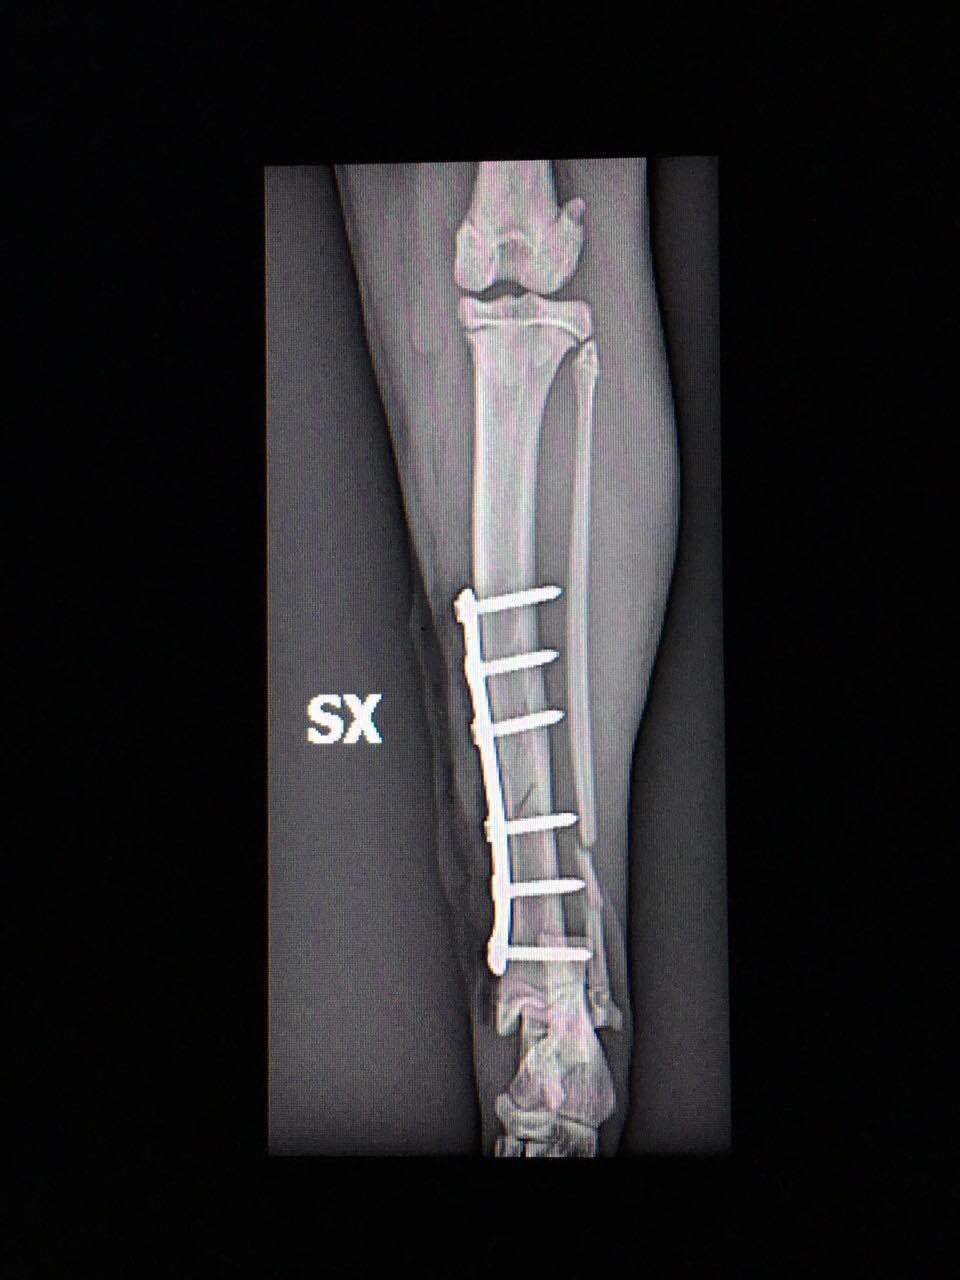

Inoltre, la scelta di mezzi di sintesi di ultima generazione come le Placche a Stabilità Angolare o i Fissatori Esterni Radio Trasparenti per i cani di taglia “toy”, permettono il miglior confort possibile per l’animale consentendone una guarigione e recupero della funzione motoria in tempi molto brevi.

A titolo esemplificativo, riportiamo due immagini